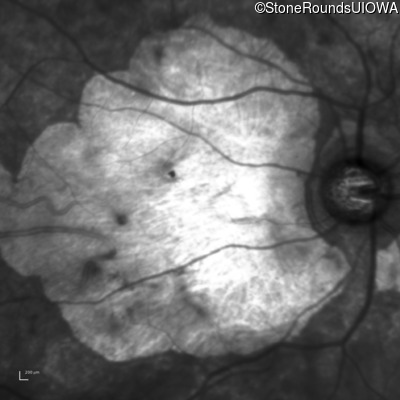

Age at visit: 43 years

OD OS